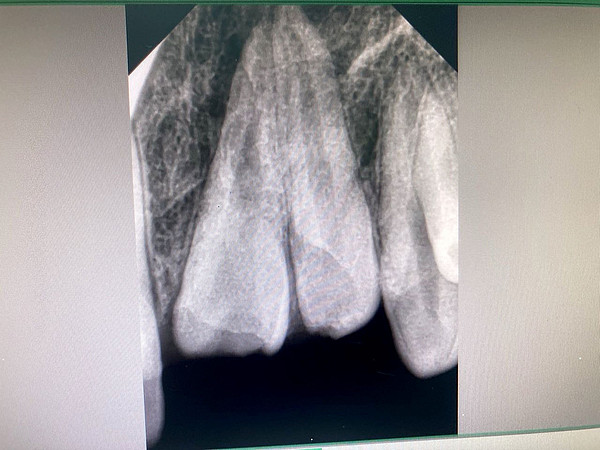

Кировские стоматологи спасли улыбку мальчика с вколоченными зубами